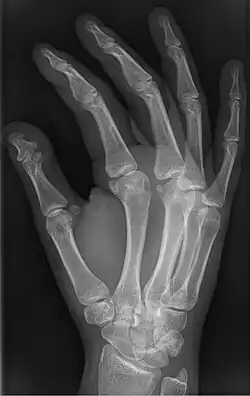

Brachyphalangy is a condition in which one or more of the phalanges of the fingers and toes are smaller than normal.[1]

This condition is one of the most common non-syndromic causes of brachydactyly and clinodactyly.